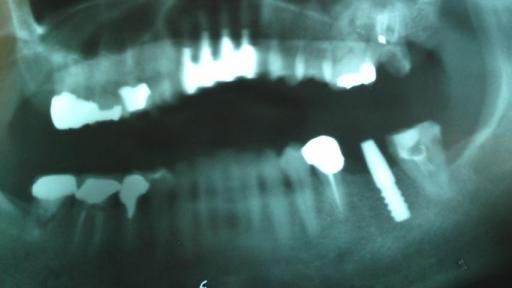

オーソドックスな インプラント症例

(多くの方の場合 このようなイージーケースになりますので 御安心ください)

左下ブリッジに噛んだ時の痛みが有る為 外して 歯のないところにインプラントを入れることにしました

骨量が充分だったので フラップレス(歯茎を剥離しない) で ごくごく短時間で治療は終わりました。 治療後も 全く痛みは無かったそうです。